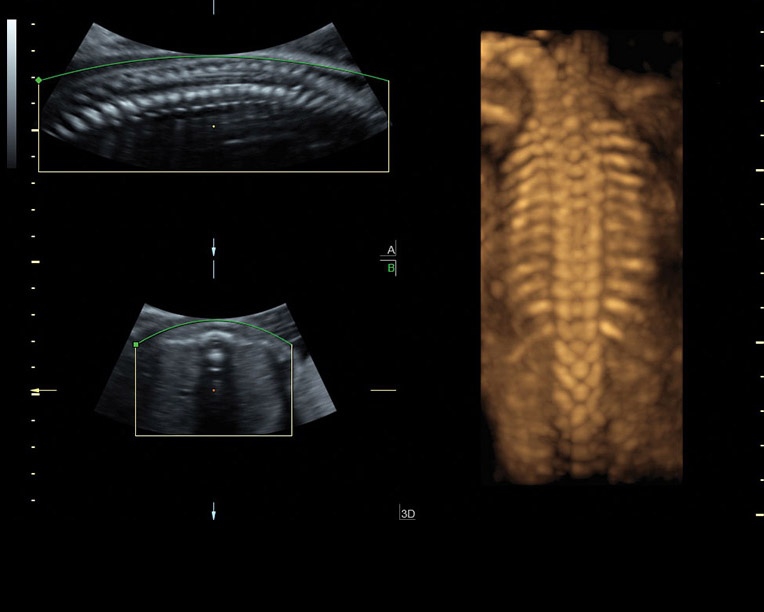

Автоматизация диагностики в аппарате Voluson P8 представлена следующими функциями:

• SonoRenderlive - повышает эффективность 3D и 4D исследований путем автоматического выбора положения плоскости визуализации. Эта функция позволяет получить наиболее четкие и детальные изображения, упрощая процесс работы врача.

• SonoBiometry - сокращает количество необходимых нажатий, предоставляя полуавтоматические измерения биометрических показателей плода, таких как бипариетальный размер (БПР), окружность головы (ОГ), окружность живота (ОЖ), длина бедра (ДБ) и длина плеча (ДП). Это ускоряет процесс измерений и повышает точность получаемых данных.

• SonoNT и SonoIT - представляют полуавтоматические стандартизированные измерения толщины воротникового пространства и внутричерепного пространства плода в I триместре беременности. Эти измерения являются важными для скрининга на хромосомные аномалии и другие патологии.

Благодаря автоматизированным функциям диагностики, Voluson P8 упрощает процесс работы врача, сокращает время проведения исследований и повышает точность получаемых результатов. Это позволяет врачам более эффективно проводить диагностику и обеспечивать качественное обслуживание пациентов.

• Педиатрия: Voluson P8 используется для исследования детей различного возраста, включая обследование органов, систем и структур внутри матки и внутричерепной полости плода.